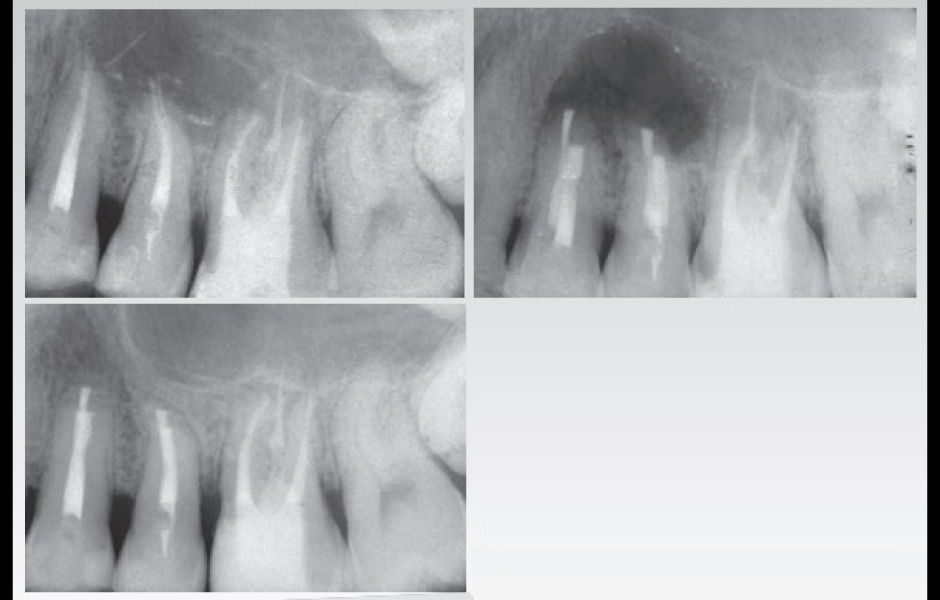

Jeho koncepty jsou postavené na jednoduše pochopitelných, snadno reprodukovatelných postupech, které přinášejí vysoce prediktabilní výsledky i v těch nejsložitějších klinických případech.

Součástí programu je také výjimečně intenzivní celodenní hands-on kurz endodontické mikrochirurgie. Nejintenzivnější praktický kurz, který byl u nás v tomto oboru organizován, si klade za cíl účastníky doslova vyždímat na retrográdním mikrochirurgickém ošetření až čtyř (!) reálných zubů, od řezáků až po horní i dolní moláry. Cílem organizátora je udělat z hands-on kurzu nezapomenutelný intenzivní zážitek, pro který nemusíte jezdit až do Florencie.

Teoretický koncept prediktabilní mikrochirurgické endodoncie od A do Z, výjimečně intenzivní hands-on kurz s operačním mikroskopem a na skutečných zubech včetně molárů.

Dr. Castellucciho přístup k mikrochirurgické endodoncii je přímočarý a čistý

…a přináší bezpečné a prediktabilní výsledky v podobě úspěšného hojení